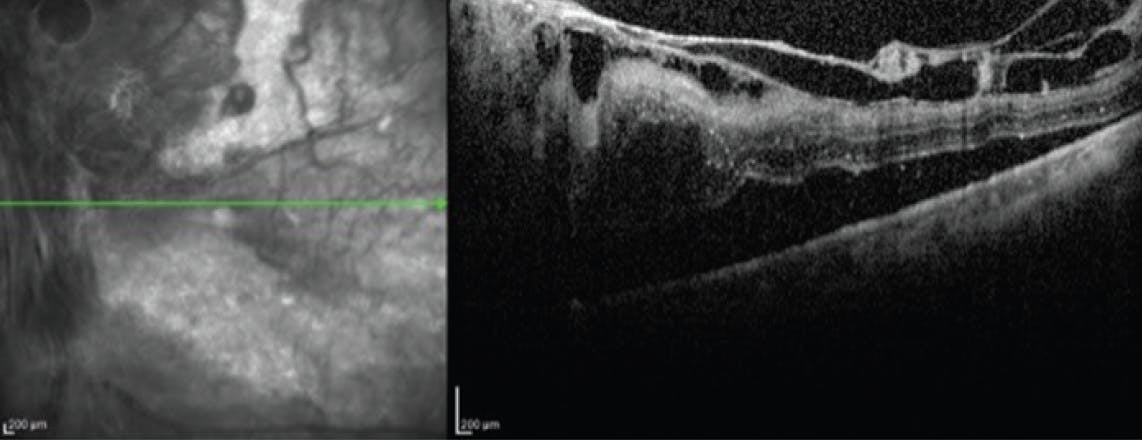

The plane of dissection is always the preretinal and sub-fibrous membrane space. Respecting this plane and selecting instruments to best achieve safe dissection is paramount to avoid iatrogenic breaks. Fortunately, most diabetic membranes are not tightly and contiguously attached to the retina. Instead, they have strong focal attachments with intervening clear areas (Figure 1). These areas can be identified and exploited to efficiently segment and remove even broad areas of fibrosis. Before segmentation, I like to use forceps to dynamically examine the membranes. By gently lifting and reflecting over the edges, I can examine the underside of membranes and identify accessible areas to advance the dissection (Figure 2).

<p>Figure 1. OCT reveals a preretinal fibrovascular membrane with focal attachments and intervening clear spaces. The clear spaces provide opportunities to propagate dissection.</p>

Figure 1. OCT reveals a preretinal fibrovascular membrane with focal attachments and intervening clear spaces. The clear spaces provide opportunities to propagate dissection.